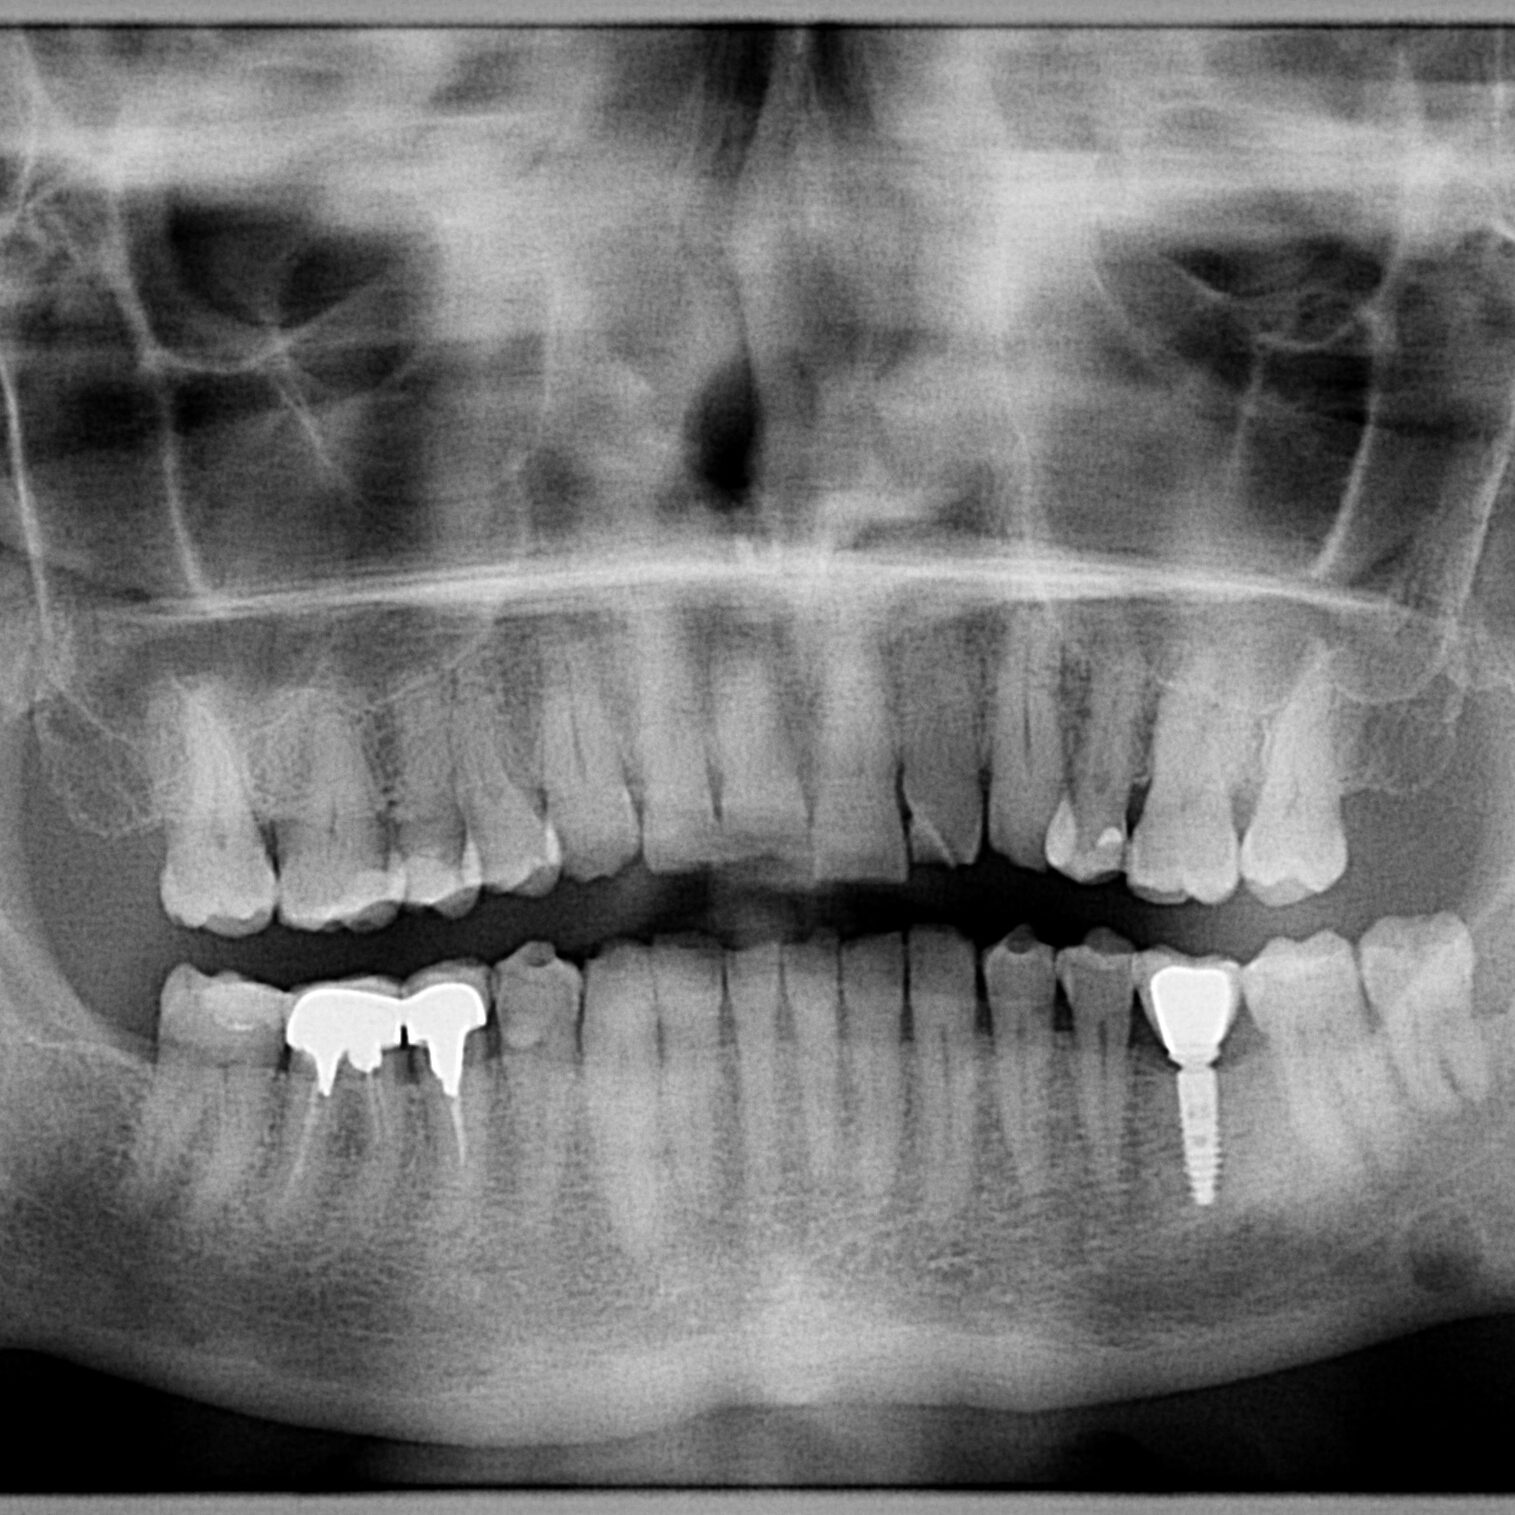

Why dental implants?

Dental implants are one of the greatest discoveries of modern dental medicine. High-quality materials ensure the natural appearance of the teeth and high functionality. In addition, dental implants protect the bone and are a long-term solution for a perfect smile that gives you a feeling of self-confidence and happiness. Dental implants are easy to clean and completely safe.